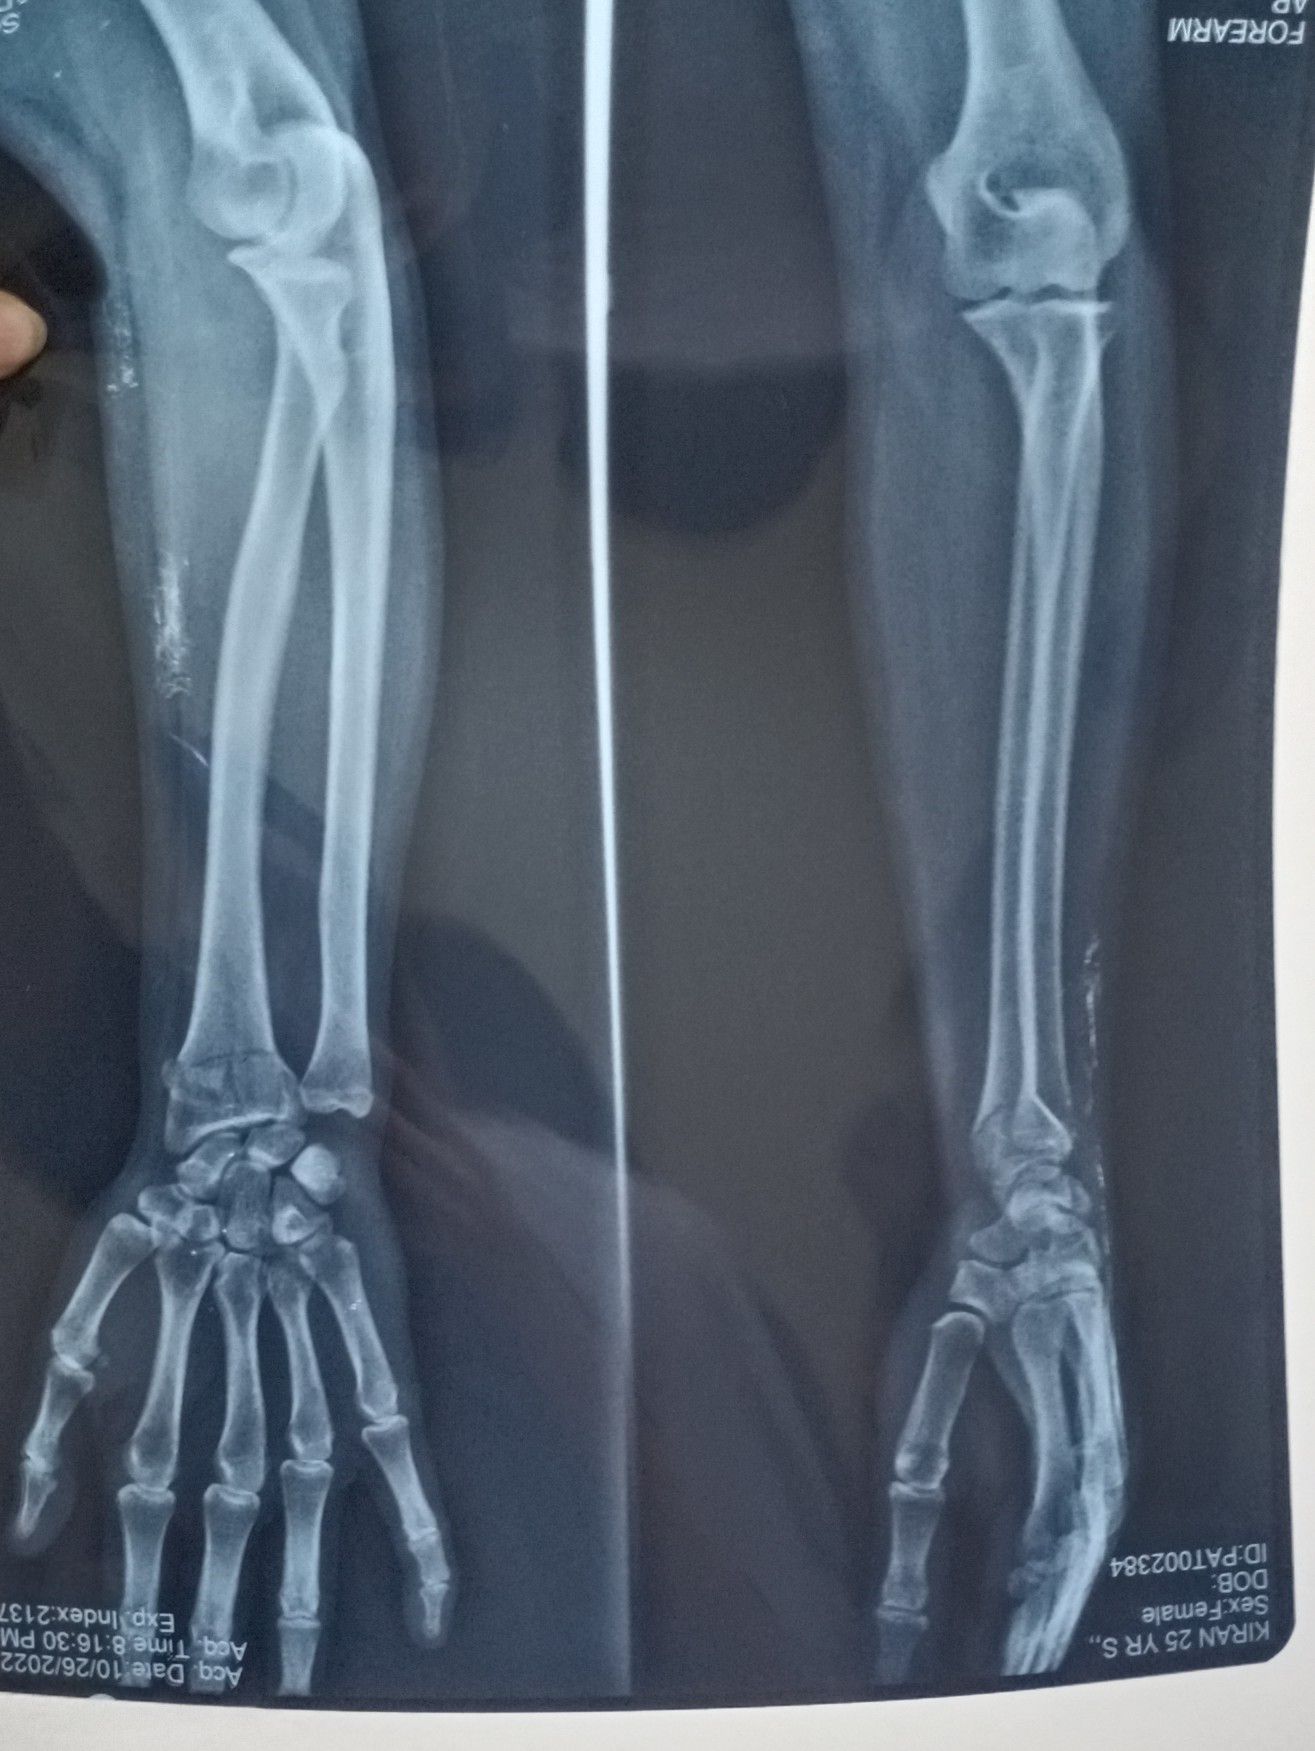

Galeazzi fracture

Stable, partially displaced fracture managed by applying cast , while displaced fractures are managed by percutaneous insertion of k-wiring and cast immobilization. K-wire is to be removed by 4-6 weeks.